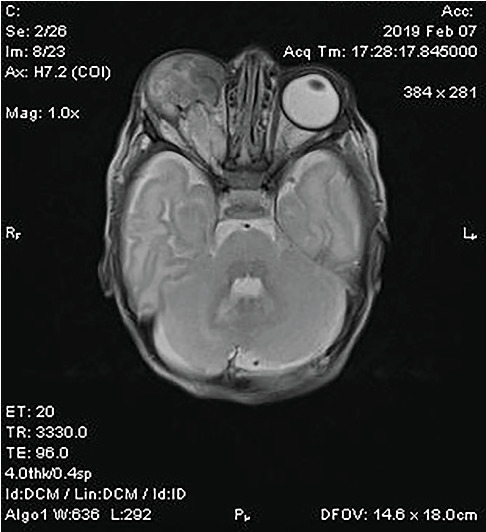

This case report describes a rare instance of primary orbital teratoma with anophthalmia in a neonate. A 6-day-old female presented with a congenital right orbital swelling and absence of visible ocular structures. MRI revealed a large, well-vascularized orbital mass without intracranial extension, accompanied by malformations in the right cerebral hemisphere. Histopathological examination confirmed a benign, mature/mixed teratoma comprising elements from all three germ layers, including neuroectoderm, mesoderm, and endoderm, with no evidence of malignancy. The patient underwent successful orbital exenteration with an implant at 3 weeks of age.